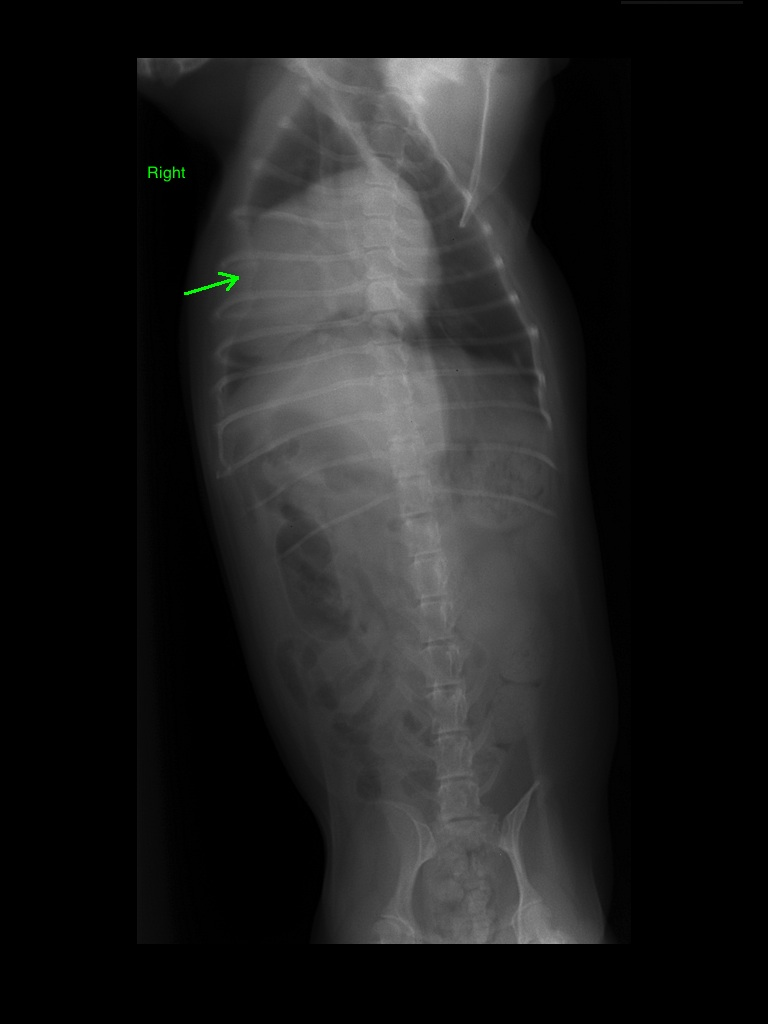

Διάγνωση: Έγινε ακτινογραφία θώρακος όπου και βρέθηκε πλήρης πύκνωση του δεξιού μέσου λοβού του θώρακα και εισολκή της κάψας του υπεζωκότα. Επειδή η αλλοίωση ακουμπούσε στο θωρακικό τοίχωμα κρίθηκε σκόπιμο να γίνει αναρρόφηση υλικού με την βοήθεια υπερήχου για κυτταρολογική εξέταση. Το αποτέλεσμα ήταν υπέρ νεοπλασματικής εξεργασίας (βρογχοκυψελιδικό καρκίνωμα). Υπήρχε μια μικρή υποψία λόγω της θέσης της αλλοίωσης πως θα μπορούσε να έχει δημιουργηθεί νέκρωση και φλεγμονή του δεξιού μέσου λοβού καθώς συνήθως είναι το μέρος που τα περισσότερα ξένα σώματα καταλίγουν εξαιτίας της λοξής πορείας προς τα πίσω του δεξιού στελεχιαίου βρόγχου, ενώ αντίθετα ο αριστερός είναι πιο κάθετος στην τραχεία. Η κυτταρολογική εξέταση απέκλεισε αυτή την περίπτωση σε συνδυασμό με την κλινική εικόνα του ασθενή.